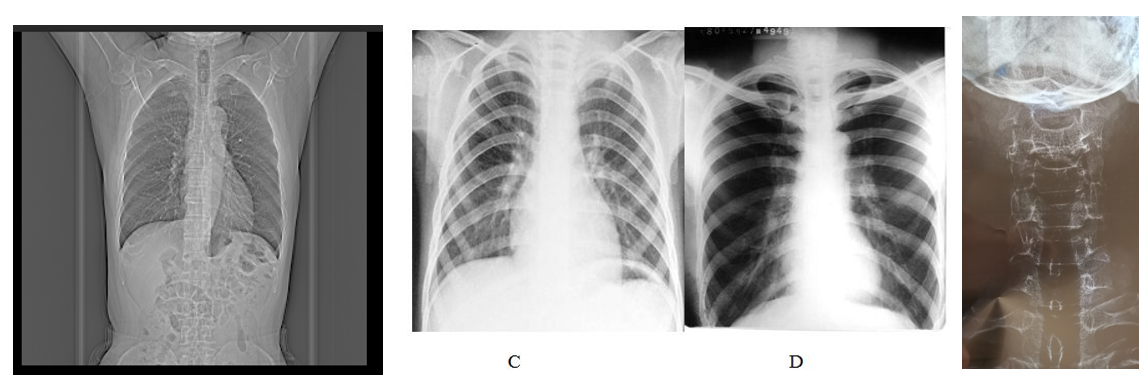

头部CT或MRI可见脑萎缩和脑室扩大,PET可显示病变区葡萄糖代谢明显下降。(图A为正常人的头部CT及PET;图B为阿尔茨海默病患者的头部CT及PET)